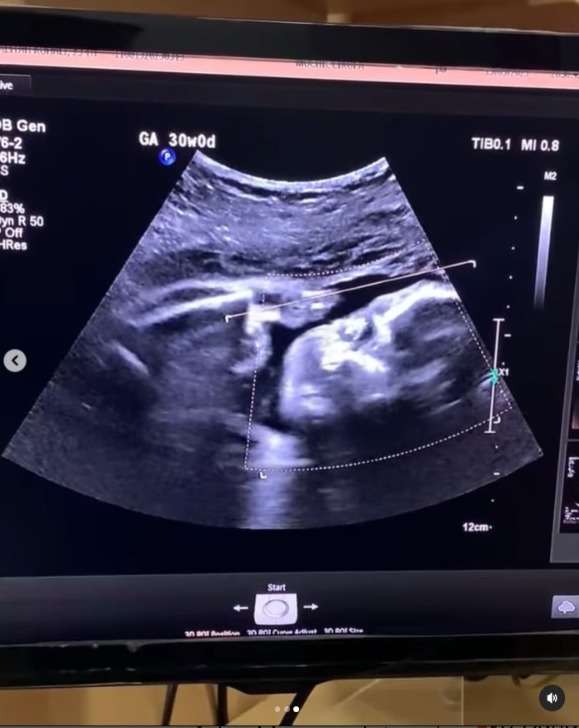

Ia mengatakan bahwa hatinya merasa bahagia saat melihat anak yang dikandungnya dalam keadaan sehat. Bahkan sang anak terlihat bergerak aktif saat menjalani USG.

“ Aku seneng banget pas usg bayiku gerak-gerak,” tulis calon ibu tersebut.

Namun, kesedihan itu langsung sirna berubah menjadi bahagia saat ia periksa usg dan melihat anak di dalam kandungannya menggerakkan tangan seperti sedang dadah ke ibunya.

Seolah bayi itu ingin memberitahu bahwa keadaannya di dalam baik-baik saja, sehingga sang ibu tidak perlu sedih dan khawatir lagi. Saking bahagianya, wanita ini sampai menangis saat melihat usg anaknya.